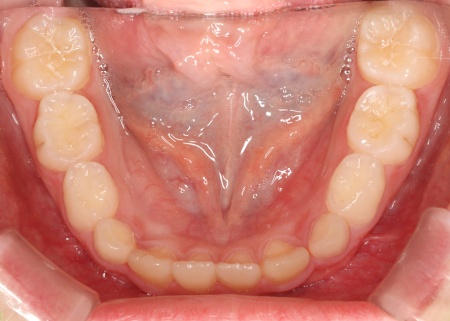

続いて下顎には、顎の幅を広げて歯が並ぶスペースを確保しながら、上下の噛み合わせのバランスを整える役割をもつ「拡大床」という装置を装着しました。

治療中は定期的に通院いただき、装置の調整を丁寧に行いながら、噛み合わせの状態を都度確認します。

お子様の成長に合わせて慎重に治療を進めることで、無理のない自然な形で歯並びと噛み合わせを改善することができました。

治療中